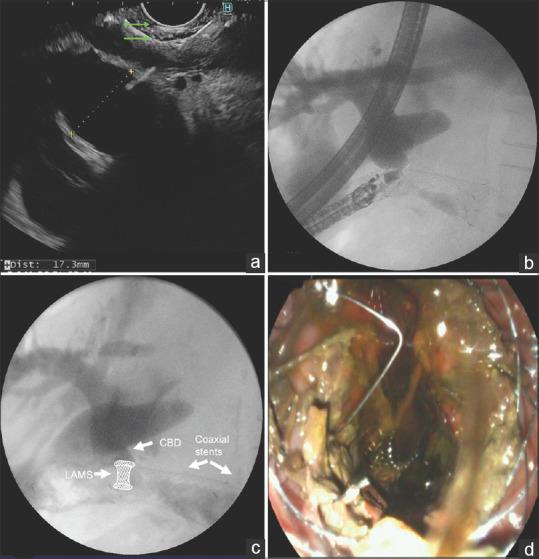

Single-stage EUS-guided choledochoduodenostomy using a lumen-apposing metal stent for malignant distal biliary obstruction.

Gastrointest Endosc. 2019 Jan;89(1):69-76. doi: 10.1016/j.gie.2018.08.047. Epub 2018 Sep 4.